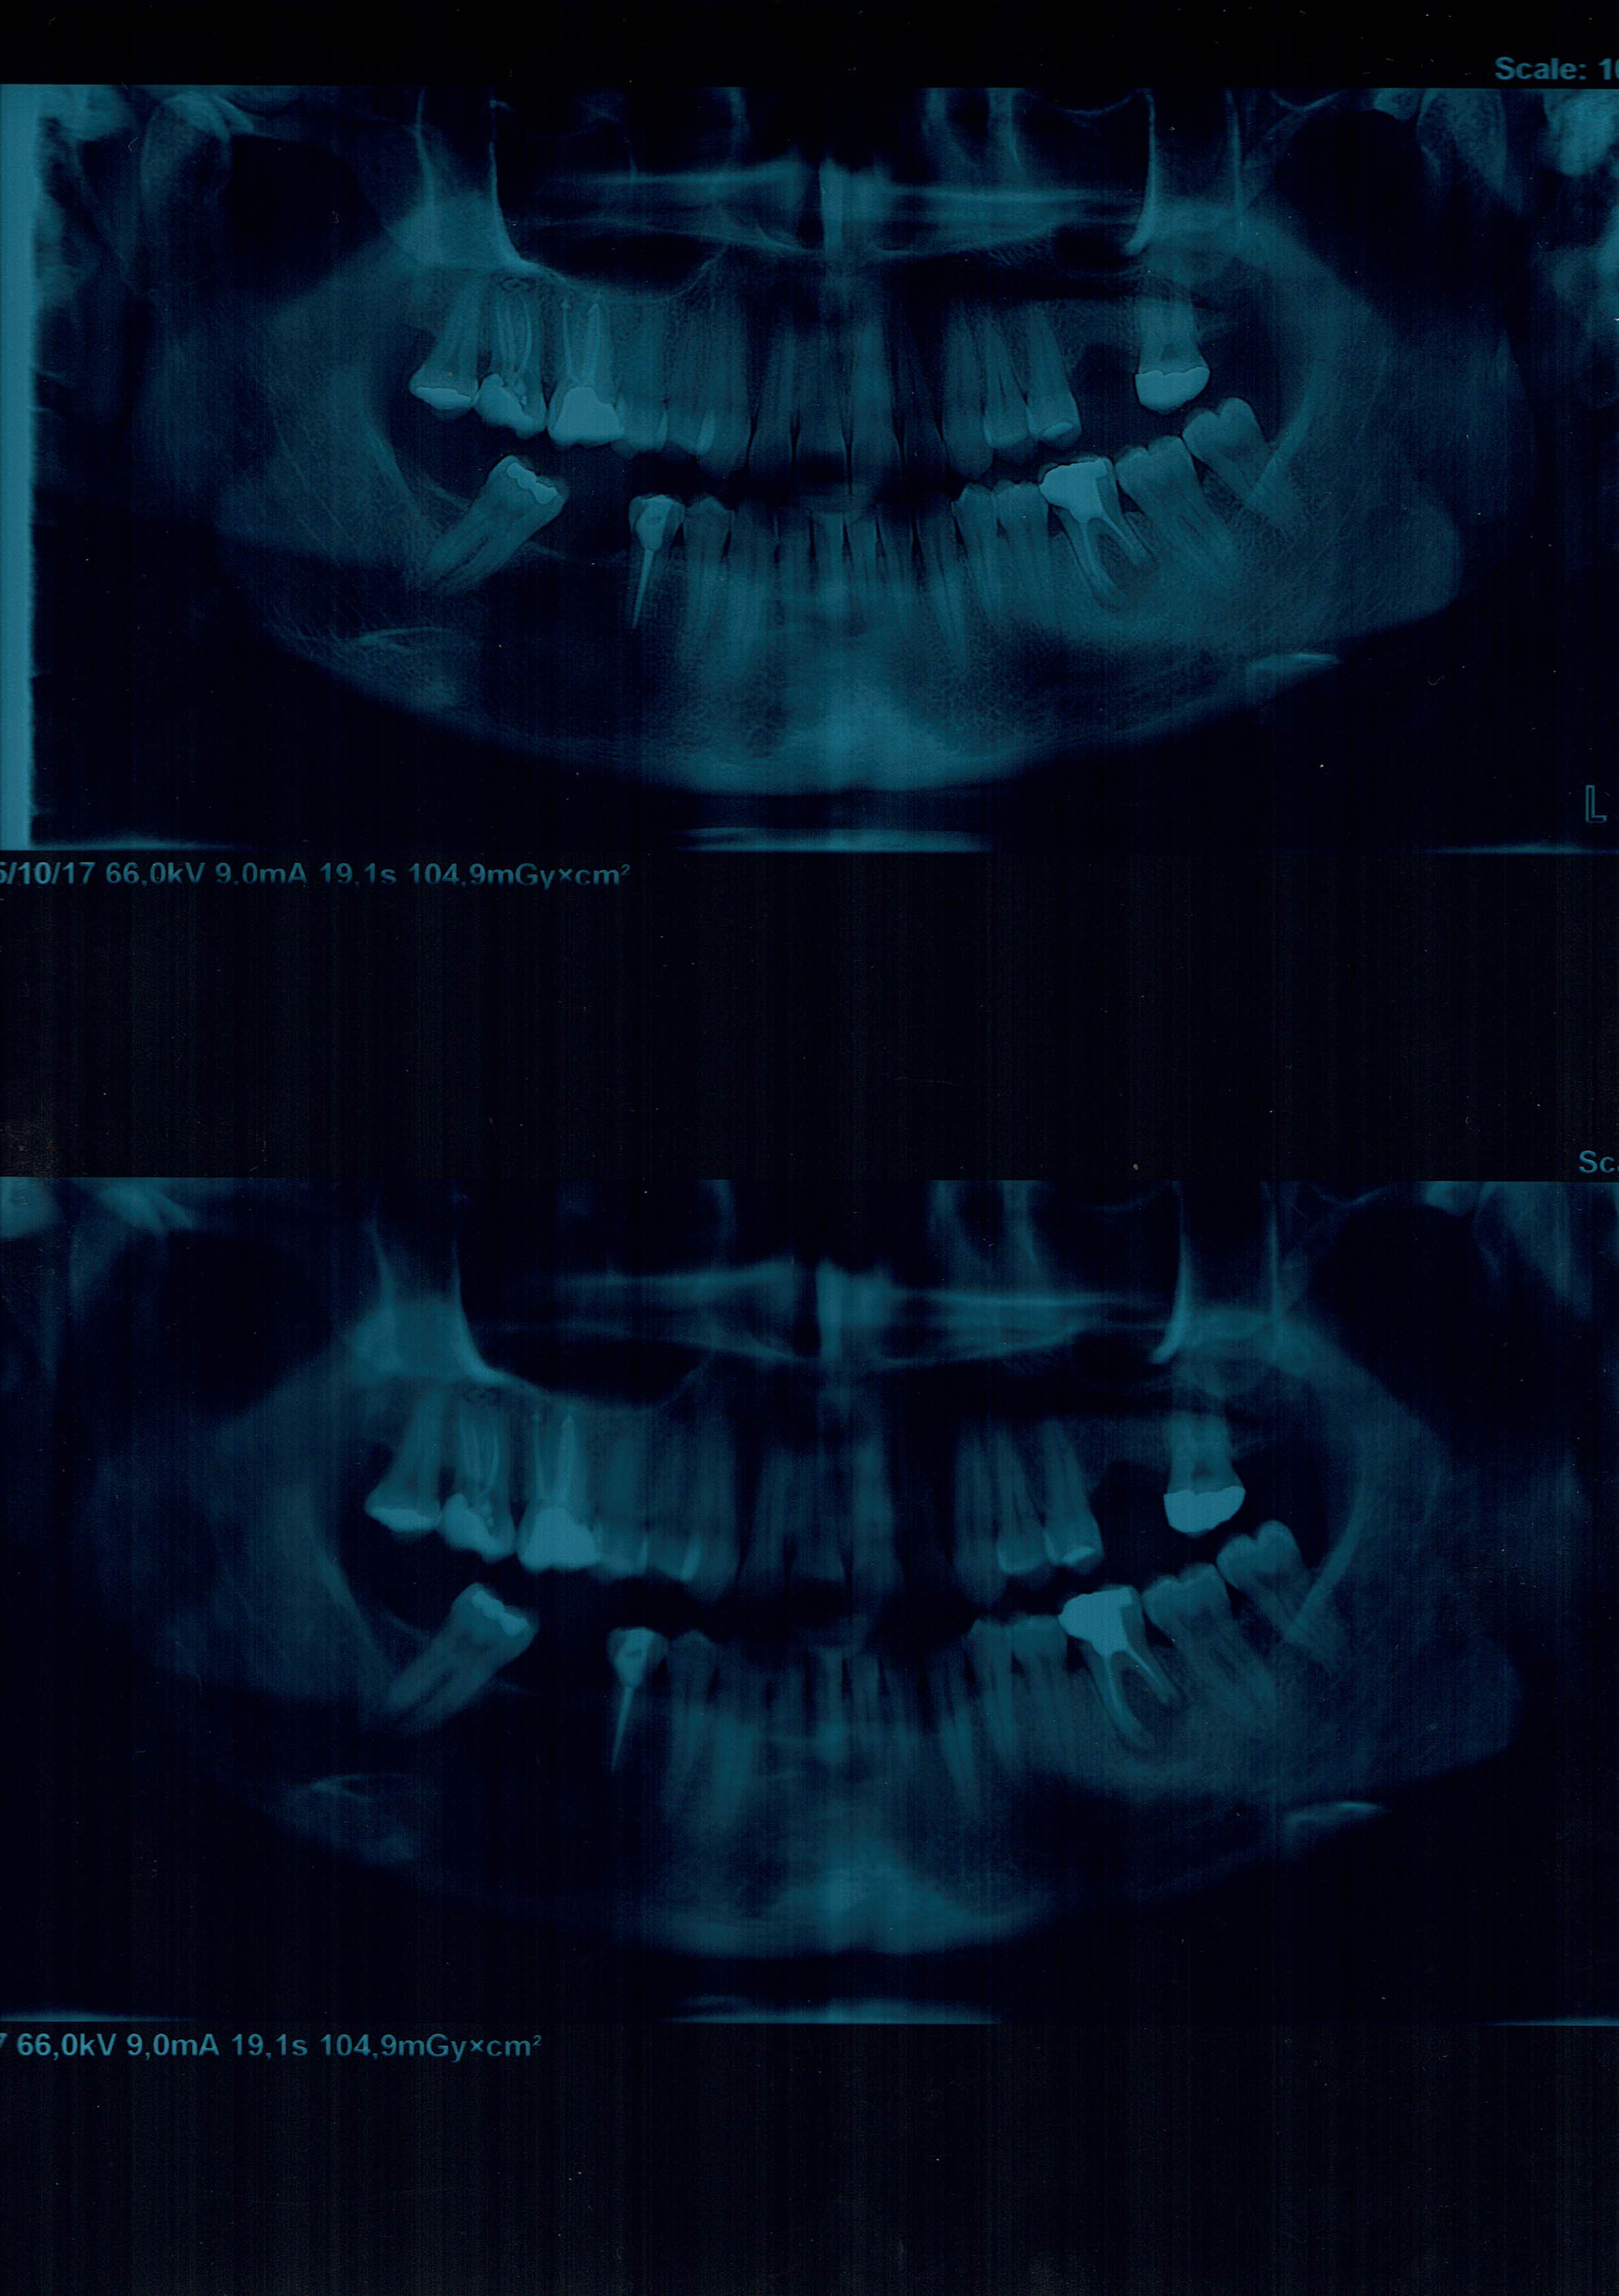

vorrei chiedere un consulto riguardo un problema che ho al 6 inferiore dx.Allego la panoramica.Ho una cisti apicale (?) sotto suddetto dente e la soluzione che mi e'stata prospettata e' l'operazione con estrazione del dente per rimuovere le cisti.Avendo gia' subito tale operazione al dente sx per la presenza di una grossa cisti (dovuta a quanto mi hanno detto ad una devitalizzazione fatta male),vorrei evitare di rioperarmi e provare a risolvere il problema con una terapia canalare.

IMG31102017_0001.jpg

[ 355.74 KiB | Osservato 1132 volte ]